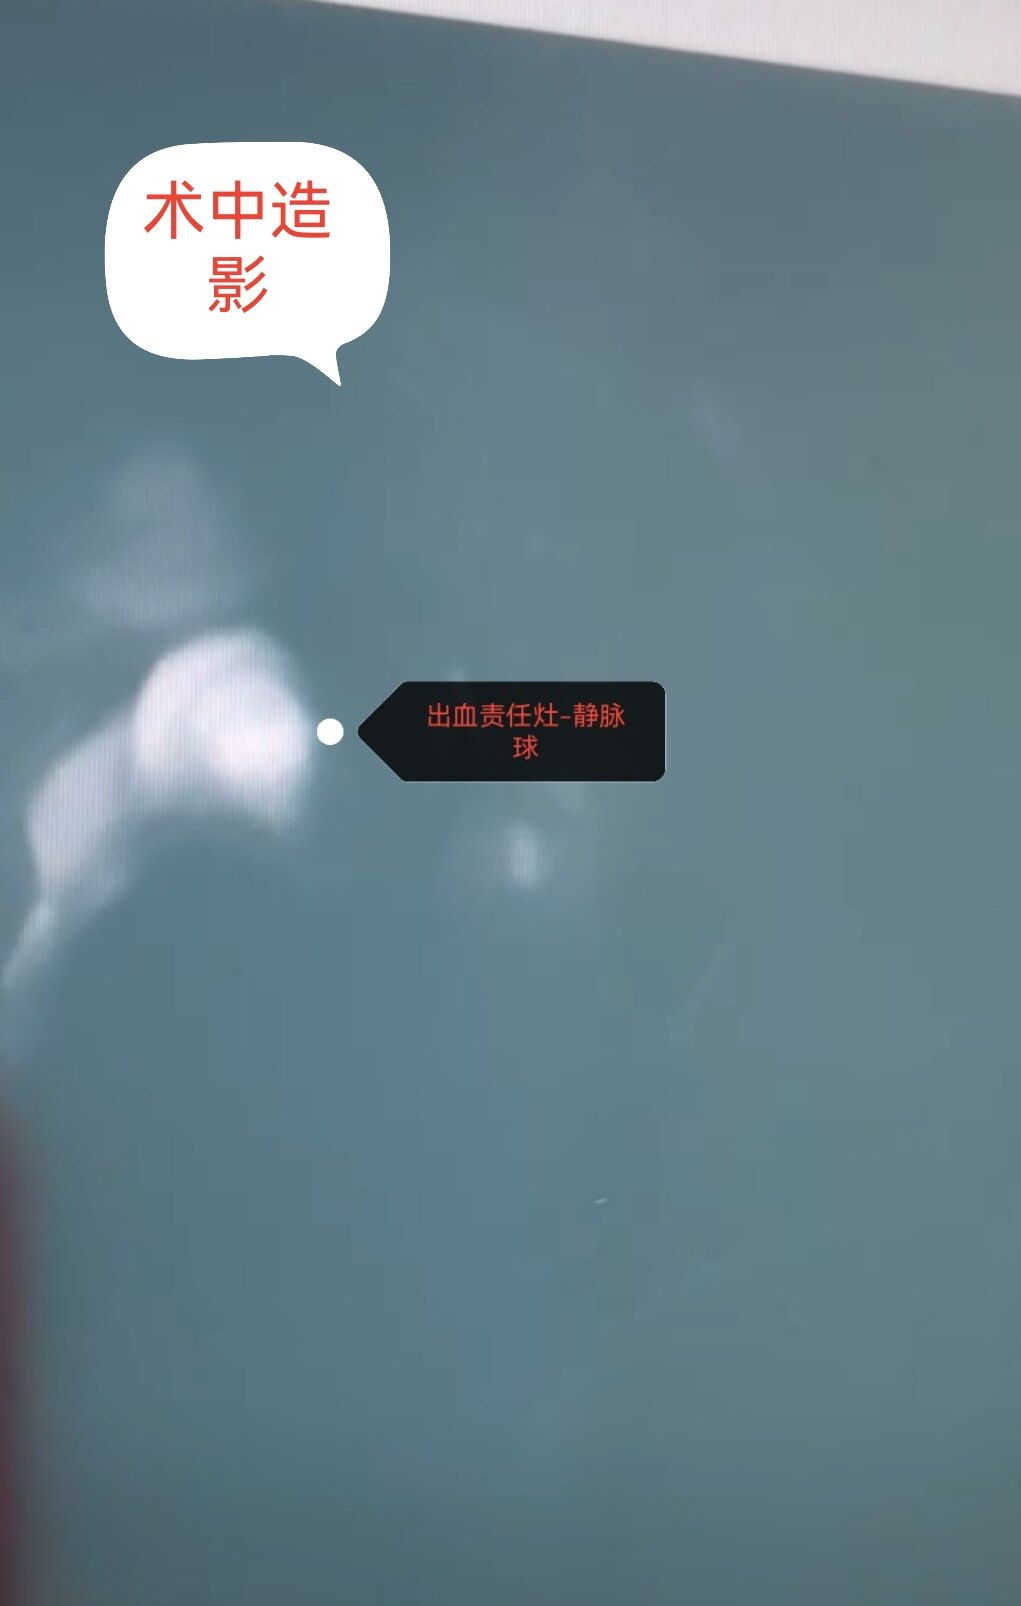

脑血管畸形主要以儿童期和青少年发病为主,儿童主要以头疼、癫痫和出血发病就诊。检查脑CTA、MRA,金标准为全脑血管造影(DSA)。治疗包括DSA介入栓塞(就是我们老百姓常说的微创手术)和开颅畸形团切除术以及伽马刀治疗,各有利弊额,也要更具患儿具体情况个性化定制治疗方案。今日展示一例8岁男童右侧枕叶脑血管畸形(AVM)破裂出血血肿急诊开颅血肿清除+荧光显微镜下畸形团全切手术。患儿入院单侧瞳孔散大,脑疝形成,已不适合介入治疗,甚至复合手术会耽搁救治。现患儿经治疗痊愈出院,无神经功能后遗症表现。后期在造影复查,修补颅骨。